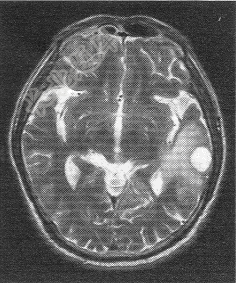

- 单项选择题患者男,72岁。肺癌术后一年余,现出现头晕头痛,MR图像如下,最有可能的诊断是

A、脑转移癌

B、脑膜瘤

C、脑胶质瘤

D、脑炎

E、脑淋巴瘤